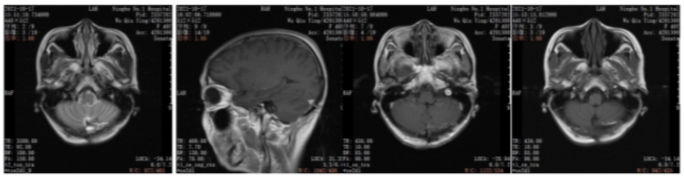

2019年10月乳腺彩超(术前):左乳实性占位(BI-RADS 4c级)。左腋下淋巴结肿大,考虑转移。

图1.乳腺彩超

本例患者术前评估左乳实性占位(BI-RADS 4c级)。左腋下淋巴结肿大,考虑转移。术后病理:ER(-),PR(-),HER2(3+),Ki67(30%)。由于患者的原因,未能做新辅助治疗,缺失了新辅助治疗后的再一次疗效评估,以及对辅助治疗的进一步决策。术后辅助治疗EC-THP(表柔比星+环磷酰胺,序贯多西他赛+赫赛汀+帕捷特),之后辅助曲妥珠单抗(赫赛汀)+帕妥珠单抗(帕捷特)靶向治疗完成1年治疗。在辅助靶向治疗后4月发现单发脑转移病灶。之后行左侧小脑半球肿瘤切除+颅底重建术。脑转移瘤瘤床区放疗。全身系统治疗:汉曲优+吡咯替尼+卡培他滨作为二线治疗,随访中已有15月的PFS,目前仍是CR状态。